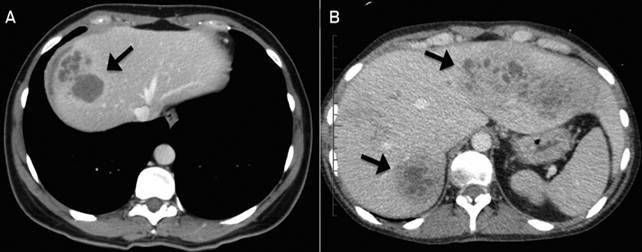

Hình 1

Việc chẩn đoán bệnh sán lá gan lớn ở người thường dựa vào phổ lâm sàng và xét nghiệm gồm có soi tìm trứng sán trong phân (song việc phát hiện trứng sán thường hiếm khi thành công vì người không phải là vât chủ chính), xét nghiệm huyết thanh miễn dịch ELISA hoặc Western blot (chỉ thực hiện tại một số bệnh viện hoặc trung tâm y tế chuyên khoa), siêu âm, chụp cắt lớp vi tính và chụp cộng hưởng từ được áp dụng phát hiện tổn thương là những công cụ chẩn đoán thường quy tại nhiều cơ sở y tế, giúp phát hiện và chẩn đoán tổn thương sán lá gan lớn rất hiệu quả. Để nhiều đồng nghiệp quan tâm đến bệnh sán lá gan lớn một cách tổng thể nhất, đặc biệt là phương diện chẩn đoán hình ảnh.